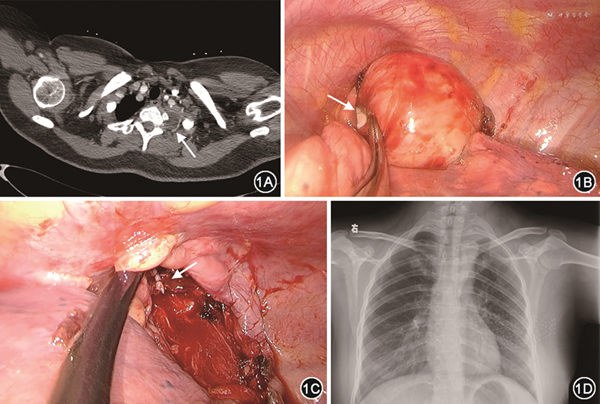

患者1 女性,27岁,主因“左侧眼睑下垂进行性加重3个月伴左上肢麻木1个月”于2017年8月7日入上海市肺科医院。患者为21三体综合征患者。入院体检:先天愚型面容,左侧眼球内陷、左上睑下垂,双瞳孔不等大,左侧缩小,对光反射存在,左上肢感觉减退。实验室检查无明显异常。CT增强扫描示左侧胸顶处占位,大小约7 cm×8 cm,肿瘤占据左侧胸廓出口,与锁骨下动脉紧邻,锁骨下动脉有一细小分支疑似穿过肿瘤上极(图1A);MRI提示神经源性肿瘤。诊断:霍纳综合征,起源于交感干的神经节细胞瘤可能。该类型肿瘤通常质地较硬且本例瘤体相对较大,从胸腔内处理如果损伤胸顶锁骨下细小分支引起出血,则术野暴露及出血控制会比较困难。该肿瘤为良性肿瘤,经影像科、胸外科、手外科等多学科诊疗团队评估后决定优先处理肿瘤上极,后通过单孔胸腔镜处理肿瘤下半部分。于2017年8月11日行锁骨上切口联合单孔胸腔镜胸顶肿瘤切除术。双腔管插管全身麻醉后,取仰卧位,患侧胸部垫高,头转向健侧,患侧左手臂外展,消毒颈部区域后铺巾,于左侧颈部锁骨上方做一长8 cm切口,自此切口逐步向胸顶游离。首先游离出锁骨下动脉,探查其下为肿瘤顶部,质地较硬;仔细寻找到锁骨下动脉细小分支,见该血管紧贴肿瘤上极,两端分别双线结扎后切断。橡胶带牵拉锁骨下动脉,继续向脊柱侧逐步分离,分离出C5~T1神经根,分别予橡胶带牵拉暴露。手指钝性分离肿瘤顶部,向胸腔内压入。此时肿瘤上极与胸顶大血管和臂丛神经根完全分离。无菌纱布覆盖颈部切口后更换为右侧卧位,左手臂悬吊,打开颈部切口覆盖纱布后,再次消毒下颌缘至脐平面皮肤,铺巾,暴露颈部切口和侧胸壁,自腋中线第4肋间做一长4 cm切口,逐层进入胸腔后,置入切口保护套,单孔胸腔镜操作。探查胸顶部,为肿瘤占据,肿瘤无法与远端交感干游离。胸腔内向下牵拉游离肿瘤,同时配合经锁骨上切口予手指钝性向胸腔内游离肿瘤,最后电凝钩仔细操作于胸腔内完整切除肿瘤,自胸部切口取出肿瘤(图1B、1C)。肿瘤切除后,暴露胸顶后进一步探查,见胸廓入口处交感干位于肿瘤起始部,远端随肿瘤切除后局部缺如(视频1)。胸腔内留置胸管1根,自胸部切口引出,颈部切口一期皮内缝合不放置引流。颈部游离操作时间1.5 h,单孔胸腔镜切除肿瘤1.0 h,术中出血量20 ml。术后第1天复查胸部X线片,左肺复张良好引流少,拔除胸管,术后第3天出院。病理学检查证实为节细胞神经瘤。术后1个月随访胸部X线片显示恢复良好(图1D),左上肢麻木感消失,霍纳综合征未改善。由于患者依从性较差,未再通过门诊随访,电话随访情况稳定。